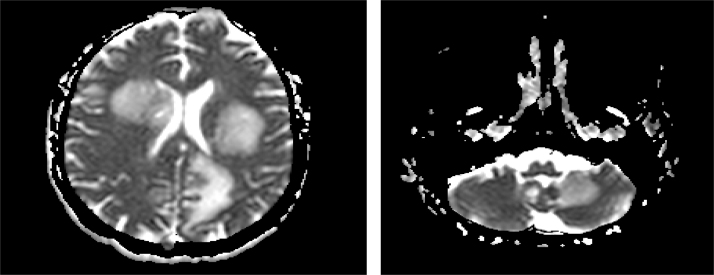

Fig. 3.

A and B. Representative axial images of MRI of the brain showing innumerable ring enhancing lesions with surrounding edema in both cerebral hemispheres (A), bilateral basal ganglia, midbrain and cerebellar hemispheres (B).

A 34-year-old Indonesian male presented with a four week history of diffuse abdominal pain, nausea, vomiting, odynophagia, dyspnea on exertion, and a 20-pound unintentional weight loss. The patient had a past medical history significant for intravenous drug abuse, alcohol abuse and 15 packs per year smoking history. The patient had moved to United States from Indonesia 7 years ago. Physical exam revealed a cachectic male with oropharyngeal candidiasis and crackles bilaterally. Diffuse abdominal tenderness on palpation was also noted. Laboratory studies revealed a normal complete blood count (CBC), hyponatremia with sodium of 122 mEq/L, and abnormal liver function tests: AST 442 U/L, ALT 150U/L, and ALP 295 U/L. A fourth-generation HIV antigen/antibody test (Abbott Laboratories) was confirmed positive with a MultiSpot positive for HIV-1 antibodies. Hepatitis C antibody testing was also reactive. Additional testing revealed a CD4 count of 2 cells/mm3 and a HIV-1 titer of 427,000 copies/ml determined by a Quantitative HIV-1 RNA PCR assay (COBAS AmpliPrep/COBAS Taqman Analyzer, v2.0, Roche Diagnostics). Chest imaging was concerning for either multifocal pneumonia and/or possible opportunistic infection (Fig. 1A). Abdominal CT revealed necrotic mesenteric lymphadenopathy (Fig. 1B), micro-abscesses in the liver (Fig. 1C), and a 2.9 × 2.4 × 2.0 cm fluid attenuation collection posterolateral to the prostate suggestive of an abscess (Fig. 1D-E). Urine analysis showed 2+ protein, 1+ urobilinogen, 3 red blood cells, and 2 white blood cells. Multiple routine urinary cultures showed no growth. Three sputum samples were collected and all showed 4+ acid-fast bacilli (AFB) (> 36 AFB organisms per field of view at 400 × magnification) by auramine-rhodamine stain and grew pure Mycobacterium tuberculosis complex in less than 7 days post-collection in the BACTEC ™ Mycobacterial Growth Indicator Tube (MGIT). Following culture, drug sensitivity testing was performed, and the mTB isolate was susceptible to first line drugs, including isoniazid (MIC-0.2 mcg/mL), rifampin (MIC-1.0 mcg/mL), ethambutol (MIC-5.0 mcg/mL), pyrazinamide (MIC-100 mcg/mL) and streptomycin (MIC-2.0mcg/mL). The patient was started on rifampin–300 mg twice daily, isoniazid–300 mg daily, pyrazinamide–1500 mg daily and ethambutol–1200 mg daily (RIPE therapy). Antiretroviral therapy was not initiated at this time. Twelve days later, on follow-up imaging, the prostatic abscess remained unchanged and a CT guided approach was utilized to drain the abscess. Purulent fluid (2 mL) was drained and sent for AFB culture. The purulent fluid revealed 4+ AFB by auramine-rhodamine stain (Fig. 2A) and grew mTB complex. The direct Kinyoun stain is shown in Fig. 2B. Patient clinically improved on RIPE therapy and was discharged with isolation precautions. 3 weeks post discharge, antiretroviral therapy with dolutegravir and Truvada (HAART) was initiated. Post-discharge (28 days), the patient was brought to the emergency department with acute onset of drowsiness and incomprehensible speech. The patient had been compliant with his medications. At this point, differential diagnosis of Immune reconstitution inflammatory syndrome (IRIS), and a new opportunistic infection including toxoplasmosis were considered. MRI of the brain revealed multiple ring enhancing lesions with surrounding edema in the cerebral hemispheres bilaterally, the midbrain, and the cerebellar hemispheres bilaterally as well (Fig. 3A,B). The patient was started on steroids, empiric toxoplasmosis therapy with pyrimethamine, sulfadiazine, and folinic acid. HAART and mTB therapy were continued. A lumbar puncture was performed that showed cerebrospinal fluid glucose of 54, protein of 116, RBC count of 7, and WBC count of 0. The cryptococcal antigen was non-reactive. Toxoplasmosis IgG was >5; however, Toxoplasma gondii PCR was negative. The patient’s hospital stay was also complicated by both hyponatremia and also hypertension attributed to SIADH. The patient gradually improved on the aforementioned therapeutic regimen and nearly two months later, brain MRI showed a decrease in the size of the lesions. The patient’s mental status also improved and the patient was deemed fit for discharge. The patient was lost to follow-up after relocating to another state.